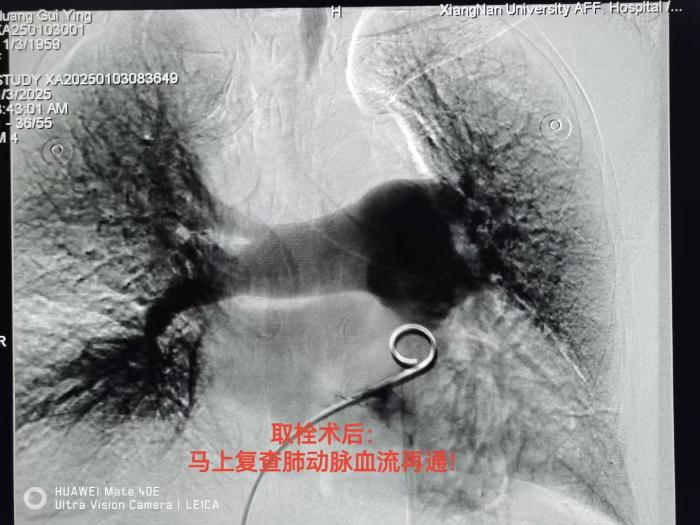

随后,医务人员凭借着精湛的技术,将导丝导管顺利探入肺动脉。肺动脉造影图像令人揪心,大量血栓充斥其中,所幸黄阿姨顽强抵抗到了救治时刻。医生们紧密配合,通过导管全力抽吸血栓,十几块无菌纱布瞬间被染成红色,见证了手术的紧张与关键。对于残留的微小血栓,医生留置导管回病房进行药物溶栓,确保彻底清除隐患。

经过3天的溶栓治疗,黄阿姨的胸闷症状消失,复查造影显示肺动脉已恢复通畅。又经过两天的观察,1月6日清晨,黄阿姨终于康复出院,迎来了崭新的生活。